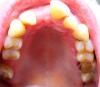

Shushek Опубликовано 9 апреля, 2013 Автор Поделиться Опубликовано 9 апреля, 2013 Снимок Ссылка на комментарий

Shushek Опубликовано 9 апреля, 2013 Автор Поделиться Опубликовано 9 апреля, 2013 Была я у ортопедов, они от моих "зубьев" в шоке, кто-то говорил удалить 21, иначе ниче не сделать, он стоит очень криво, другие ну очень с напрягом говорят, ну постараемся. Я конечно все понимаю, сама виновата. Носила когда то пластины, но ничем они мне помоч не смогли, на то время мне ничего другого наши ортодонты не могли предложить. А вот аукнулось мне все это после того, как я побежала протезироваться, но что теперь "пилить опилки", от этого легче не станет. 16 мне удалили, сейчас ортодонт, говорила еще удалить 26, ртопед говорит можно коронку и 37, насчет 21, 22 , 12, говорят сложно, у 23 оголяется корень. Вчера ходила на проф чистку, стомотолог нашел кучу маленьких дырочек . Вообще сама я склонясь больше к ортодонтии, там резец 13 стоит ближе к центру, а 12 стоит ребром, но вот я дума выдержат ли мои зубы такую нагрузку, хотя мне ортодонт сказала, что и без брекетов они тоже могут начать шататься из-за пародонтита, типа в этом случае я ничего не теряю, разве что деньги Ссылка на комментарий